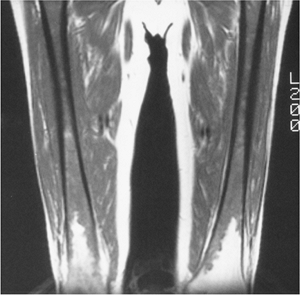

![]() |

FIGURE 12-12 Myelofibrosis. T1-weighted MR image of the femora showing low signal intensity, except distally.